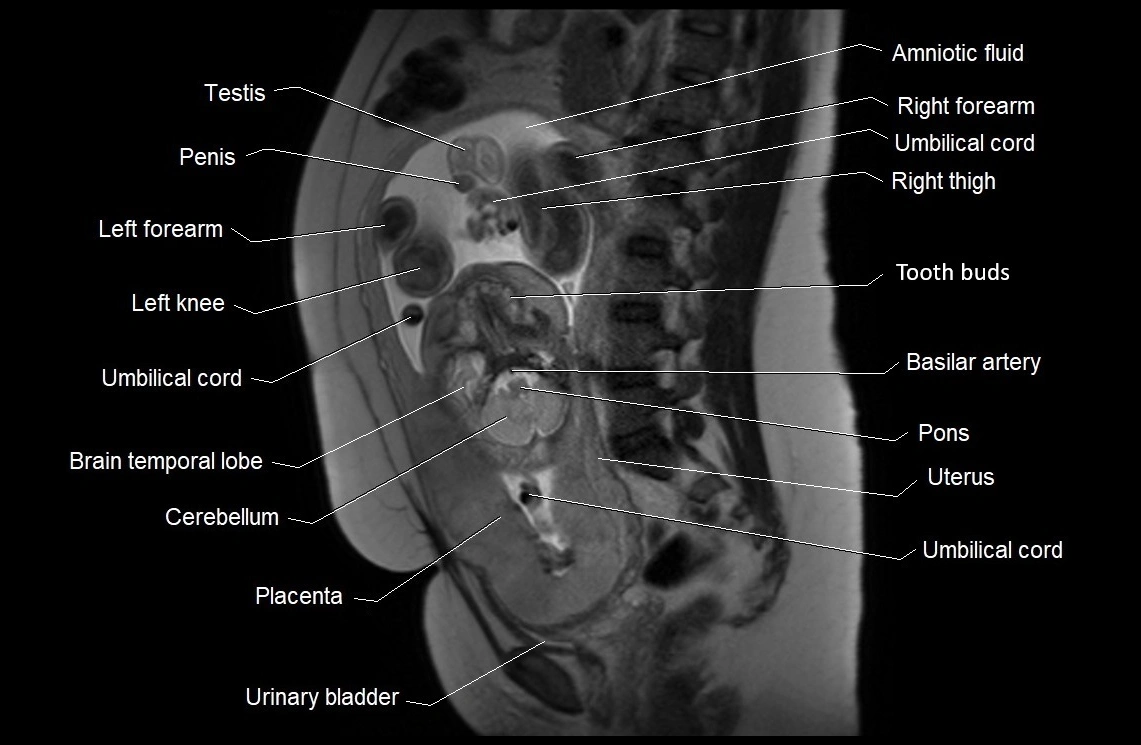

MRI Appearance

T2 HASTE (T2 GRE):

• Amniotic fluid shows very bright hyperintense signal

• Provides natural contrast against fetus and placenta

• Small particles (vernix) may appear as scattered hypointense foci within bright fluid

T1 GRE:

• Amniotic fluid shows low signal intensity (dark)

• Hemorrhage, infection, or proteinaceous content may cause focal or diffuse high signal intensity